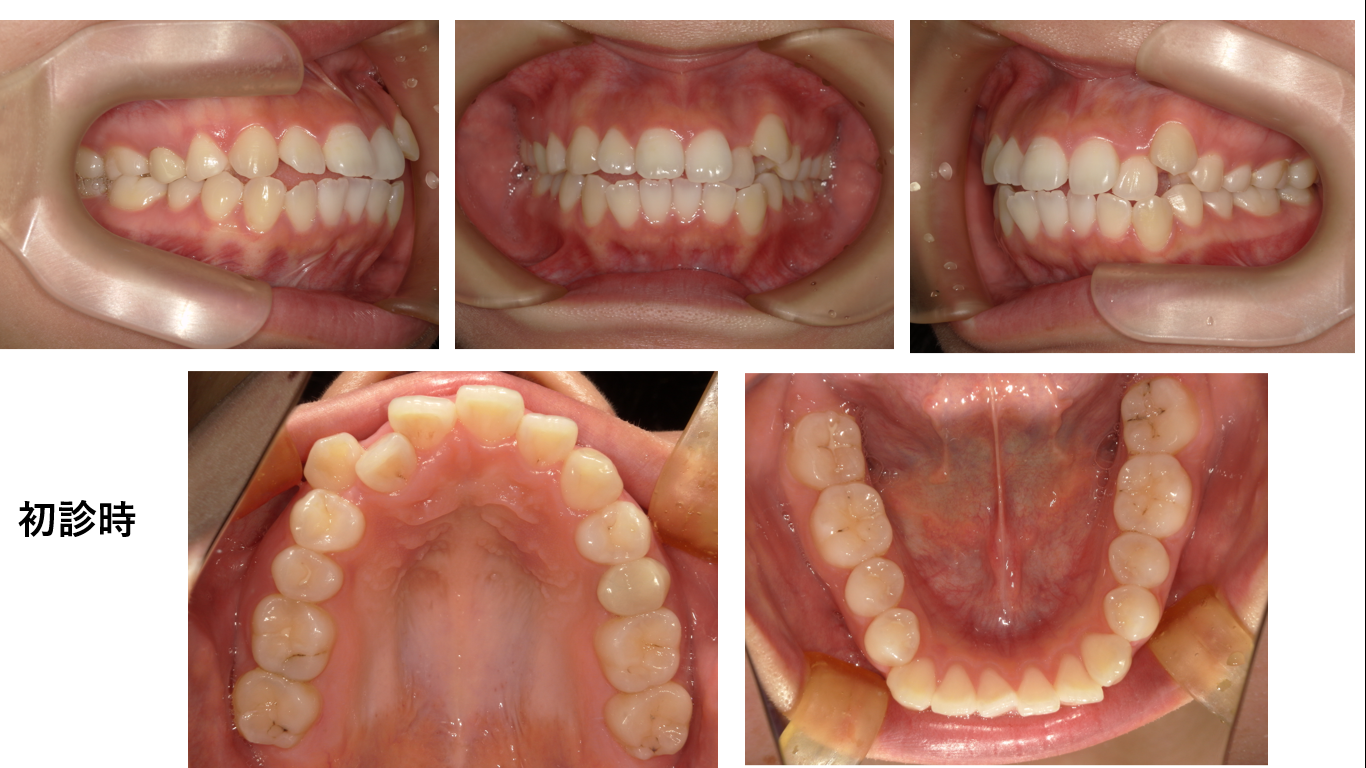

矯正症例134 AngleⅡ級2類

初診時13歳、抜歯部位:上顎左右4番、下顎左右5番、治療期間3年8か月、治療費総額112万円(税込み)歯列矯正には以下のリスクを伴う場合があります。1最初は矯正装置による不快感、痛み等があります。数日...